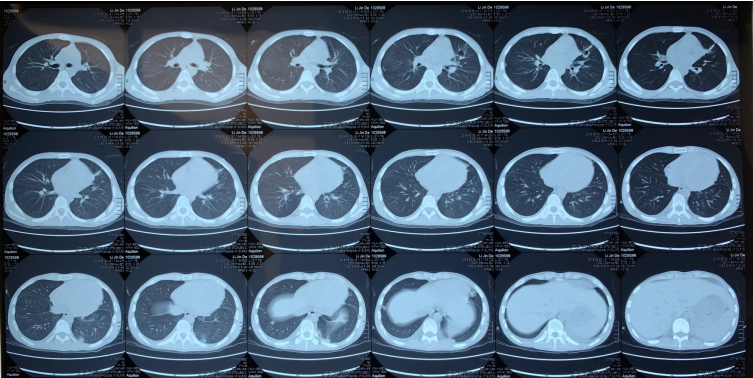

患者3月8日开始使用两性霉素B,3月12日CT显示肺部病变仍有加重;3月15日加用口服艾沙康唑后,复查胸部CT双肺渗出性病变明显好转,左舌叶空洞明显缩小,右肺实变和右肺空洞也明显吸收好转。

患者曾出现两次少量咯血,经过抗细菌感染及止血治疗后好转。2019年5月30日在大学附属第七医院复查胸部CT提示双肺病变明显好转,胸腔积液基本吸收(图7。后续患者于该院多次胸部CT复查,最后一次为2021年4月8日,显示双肺病变基本消退,左舌叶遗留薄壁囊腔,心包积液完全吸收视频5

图7  患者胸部CT(2019年5月30日)

考虑患者新发肺部病灶需要注意可能是上述抗感染药物不能覆盖的毛霉菌感染后,抗真菌药物改为泊沙康唑口服混悬液治疗,并且积极完善病原学检查明确诊断,之后也继续联合广谱抗细菌药物治疗。治疗3周后患者病情无好转,发热、咯血量增多,复查胸部CT显示肺部病变进行性进展,左肺上叶舌段厚壁空洞形成,右肺下叶空洞性病变,双肺弥漫性感染;双侧胸腔积液增多。此时痰深部真菌快速荧光染色找到毛霉菌丝,故抗真菌治疗改为两性霉素B治疗。治疗5天后再次复查胸部CT仍显示肺部病变进展,右侧胸腔积液真菌快速荧光染色也找到毛霉菌丝,两次胸腔积液培养出小孢根霉菌。此时患者家属自行购买到艾沙康唑胶囊并开始给患者口服使用。经过两性霉素B(用药19天)联合艾沙康唑(用药12天)治疗后复查胸部CT显示肺部渗出性病变和空洞性病灶明显吸收好转。后续出院后继续使用艾沙康唑治疗共6个月,复查双肺病变基本消退,仅遗留左舌叶薄壁囊腔图8。系统性红斑狼疮在风湿免疫科随访和调整相应药物下也控制稳定。

图8  患者胸部CT总结